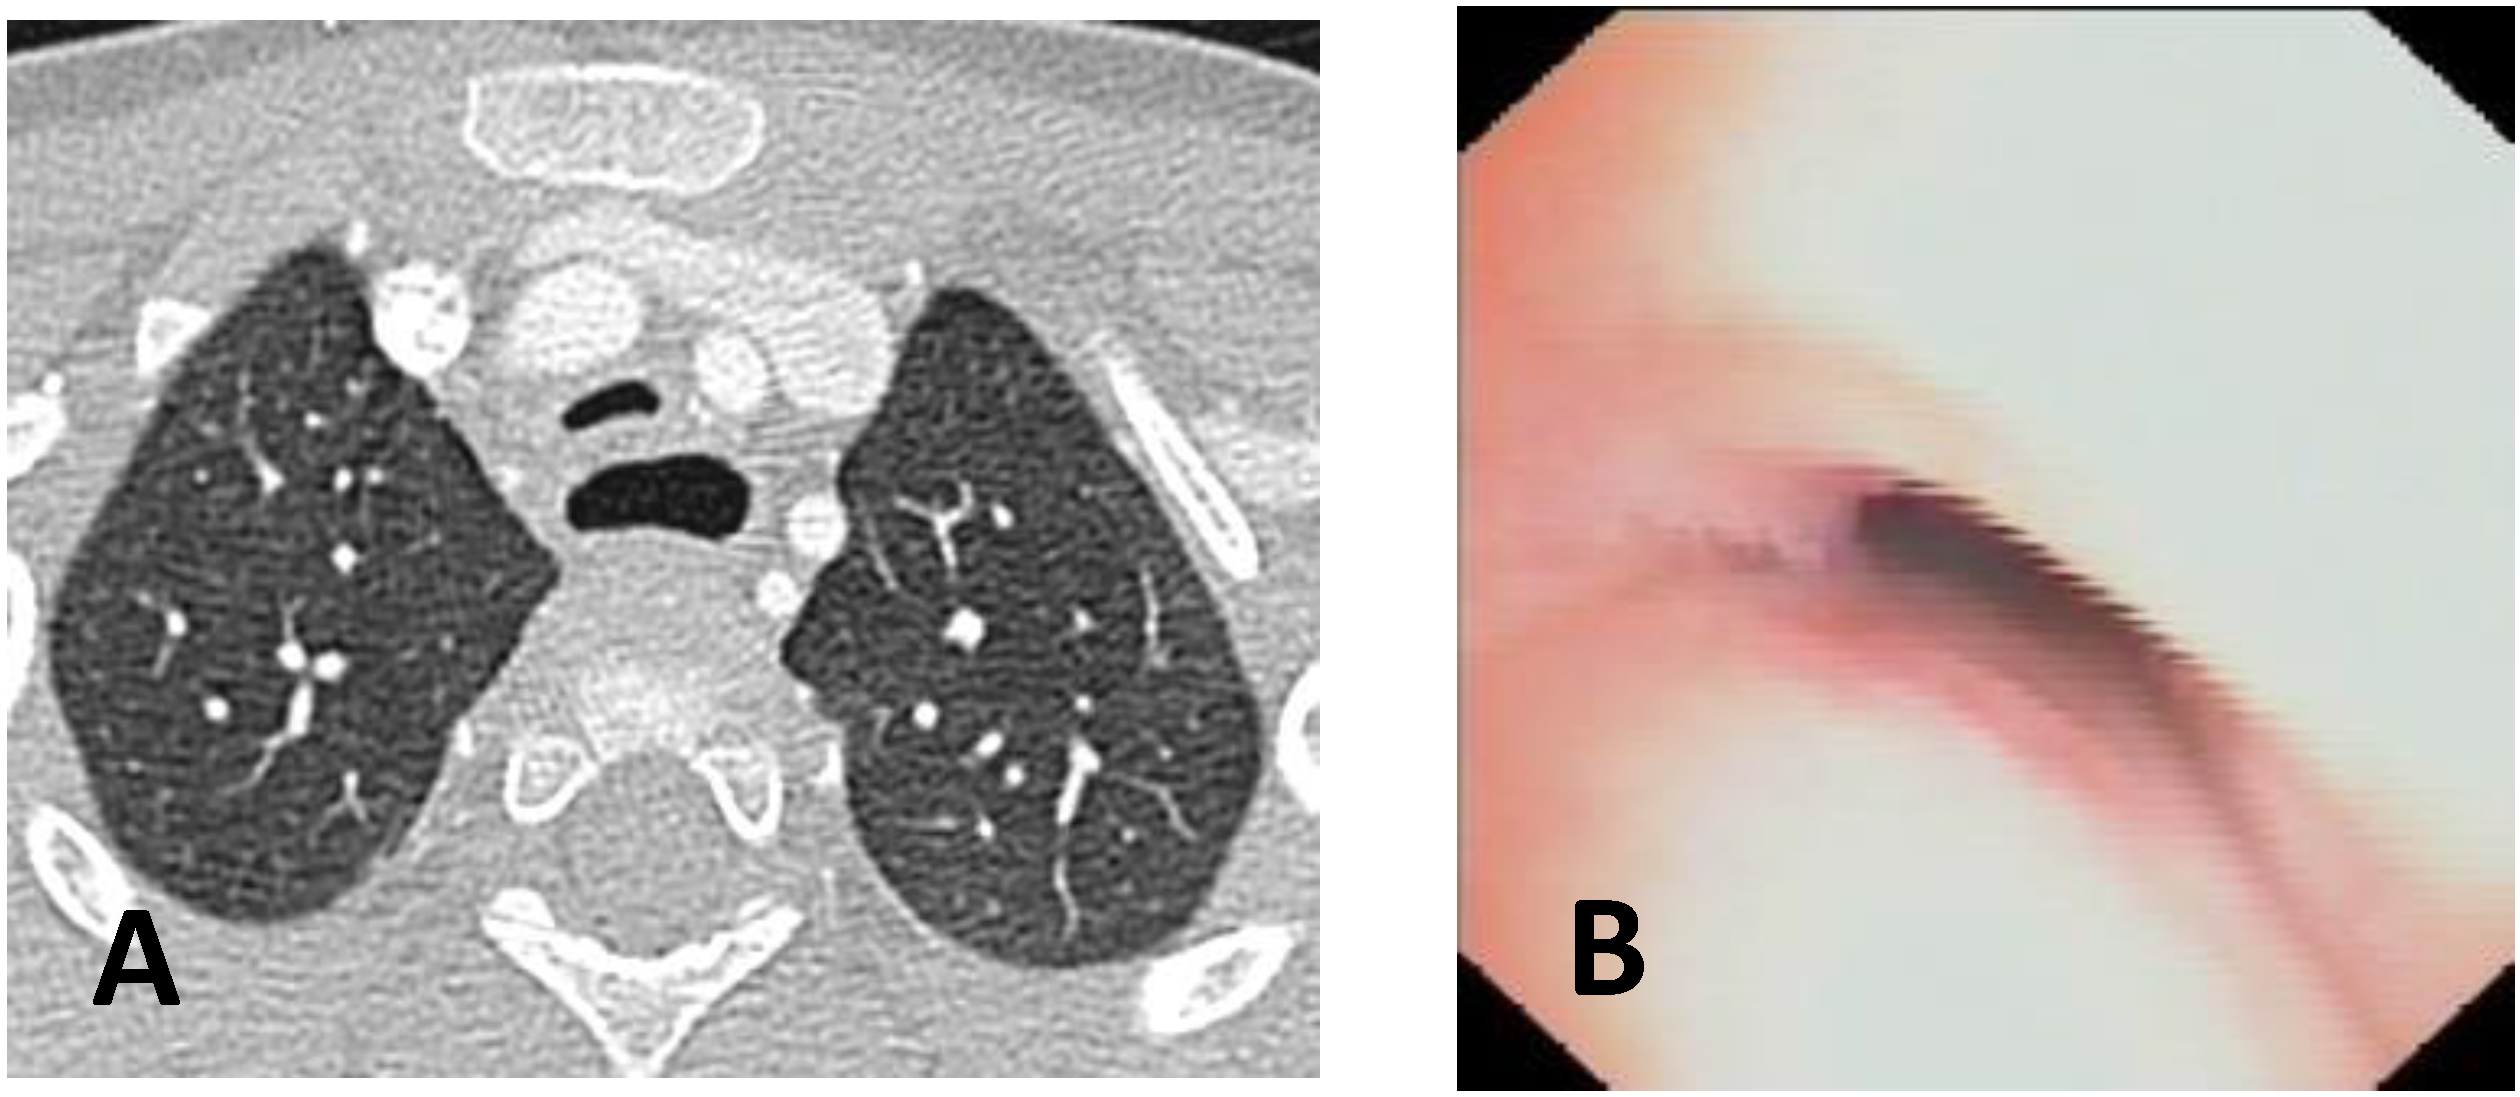

- Computed Tomography (CT): This is a continuously evolving imaging technique, rapid and non-invasive, providing an excellent overall view, independent of body size, with high spatial/temporal resolution. It allows multiplanar and volumetric reconstructions (MPR, MinPR, MipPR, and Volumetric 3D). It can be performed on children of all ages; anesthesia/sedation may be necessary under 5 years of age. Flash Monophasic Technique performed with a single scan, after intravenous injection of CM, provides information on airway morphology (but not dynamics), visualizing airways even distal to the site of obstructions and on mediastinal vessels exerting compression on the trachea or bronchi, highlighting any mediastinal pathology. CT shows cardiovascular anomalies compressing the airway, such as right aortic arch, complete/incomplete double aortic arch, pulmonary sling, and aberrant IA, all causing more or less severe TBM [16]. TM is very frequently associated with EA; CT can demonstrate malacia and extrinsic tracheal compression with a significant reduction in the tracheal ADP at the point of intersection with IA. CT can also demonstrate irreversible lung damage, such as bronchiectasis formation, caused by chronic recurrent lung infections resulting from reduced mucociliary clearance in TBM. Skeletal anomalies (e.g., pectus excavatum and scoliosis) that can cause airway compression and consequent TBM are also demonstrated. CT also evaluates tracheal compressions caused by space-occupying mediastinal lesions. Virtual bronchoscopy obtained with 3D airway reconstruction on CT images has not been very sensitive (<75%) in detecting TBM [17,18].

- Dynamic CT (DCT) allows visualization of the entire airway in a single gantry rotation using a dynamic volumetric scanning technique. Images can be acquired over one or two respiratory cycles with a total scan time of less than 2 s, while the child is breathing at tidal volume during this rapid acquisition. Anesthesia is not necessary, making the exam comfortable and drastically reducing patient discomfort. Dynamic imaging throughout the respiratory cycle allows accurate determination of end-inspiration/end-expiration phases in three dimensions (3D), with accurate determination of luminal collapse degree. The disadvantage of this technique is increased radiation dose to the patient, so it is performed only in selected cases [19,20].